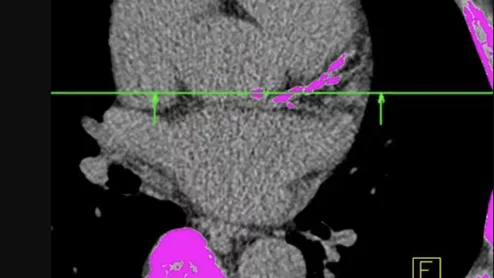

A low-dose CT coronary calcium scoring exam showing areas of calcified plaque and bone in pink.

Calcium in the coronary arteries is a known cardiac risk factor. However, new data suggest it may actually tell us more about a person's overall health than researchers previously believed.